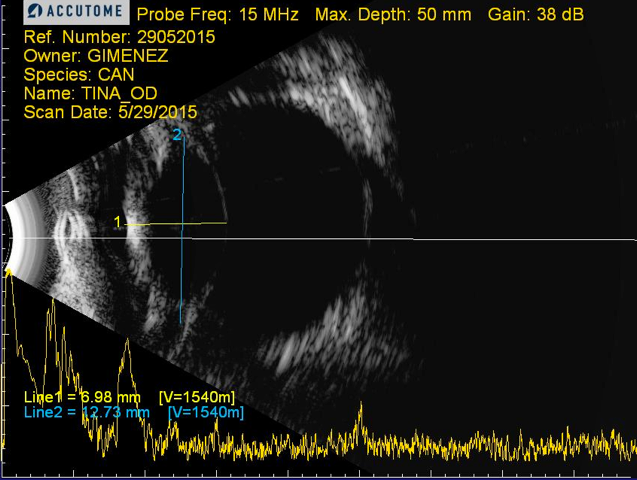

Ecografía del cristalino de Duque: 10mm en lugar de los 6-7mm de un cristalino normal. Foto:IVO

Ecografía de un cristalino de perro sano: 6-7mm. Foto:IVO